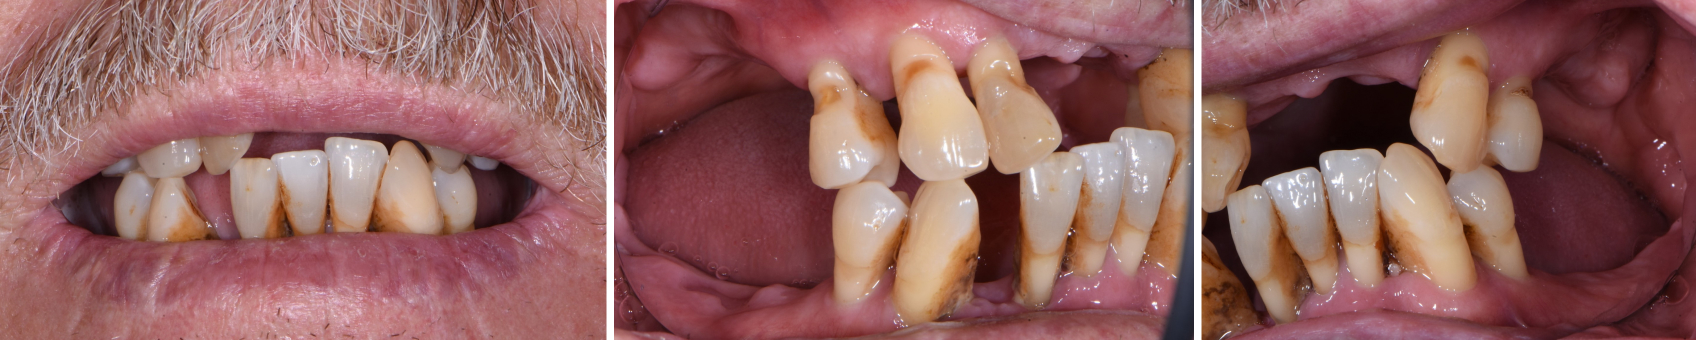

After evaluating the case further, my periodontist and I decided he would extract some posterior teeth before I scanned the patient and had the immediate dentures printed. Figs. 6–8 show the patient after those extractions; Figs. 9–14 are the scans I took.

From there, it was as simple as selecting a shade and uploading everything to the lab. Having photos of the patient’s existing teeth and face (not shared in this article for HIPAA reasons) allowed the lab to virtually extract the teeth and do a virtual wax try-in with me via team view.

Once approved, the final dentures were fully designed, printed, and returned for delivery. They looked just like traditional dentures! I’ll share an example below in the next workflow, but I have to say they fit even better and required less follow-up adjustment than traditional immediate dentures. Even my periodontist, who delivered the upper and lower dentures when he extracted the remaining teeth, was impressed.